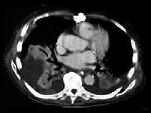

问题 87岁的甲状腺癌转移患者,傍晚行CT检查后死亡。CT图像如图所示,请选择正确的描述和结论 ( )

选项 A、考虑为右心室血栓 B、黏液瘤 C、该充盈缺损累及右心室流出道 D、未见异常发现 E、右心室见一不规则低密度充盈缺损

答案 ACE